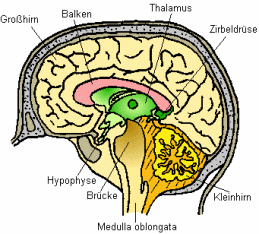

[Das im Blut gelöste

Quecksilber erreicht auch das Gehirn]

Insbesondere der auf diese Weise erfolgende Übergang von

Hg-Dampf durch die Blut-Hirn-Schranke ins Gehirn (hierzu

Hursh et al. 1988) ist von toxikologischer Relevanz. Die

als Hg-Dampf wegen dessen Lipoidlöslichkeit

(Fettlöslichkeit) ins Gehirn gelangten Hg-Mengen (S.9)

können nach der Oxidation dort als Quecksilber-Ionen das

Gehirn kaum mehr verlassen. Es kommt zu Anreicherungen von

Quecksilber im Gehirn (Friberg / Mottet 1989; Kuschinsky /

Lüllmann 1989 S.531). Die Halbwertszeit von Quecksilber im

Gehirn

- also diejenige Zeitdauer, die vergeht, bis sich die

Konzentration im angegebenen Organ bzw. im Blut auf 50 %

der Ausgangskonzentration reduziert hat,

d.h., dass etwa sechs Halbwertszeiten verstreichen müssen,

bis die betreffende Substanz den Körper bzw. das Organ

weitgehend verlassen hat -

beträgt bis zu 18 Jahre (Ohnesorge 1982, abgedr. auch

1992; Sugita 1978).

Das Gehirn als eines der Zielorgane des Speichergifts

Quecksilber ist bei einer längerfristigen

Hg-Dampf-Exposition also besonders gefährdet. Durch die

spezifische Anreicherung von Quecksilber in den

Hirnarealen lassen sich die Schädigungen des zentralen

Nervensystems und die zentralnervösen Symptome erklären,

die das Krankheitsbild einer chronischen

Hg-Dampf-Vergiftung mit prägen. Angesichts der extrem

langen Halbwertszeit des ins Gehirn gelangten Quecksilbers

ist auch die Fortdauer der Symptomatik selbst nach

Beendigung der Exposition wissenschaftlich erklärbar.

Schema des

Gehirns mit Beschriftung. Auch das Gehirn ist

Quecksilberwirkungen ausgesetzt, wenn

Quecksilberdampf eingeatmet wird.